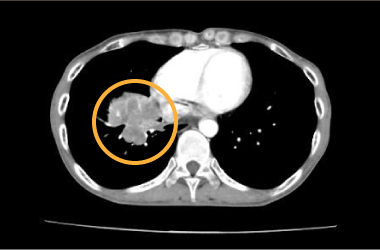

乳がん術後の胸壁再発は血管内治療の良い適応です。 全身抗がん剤が効きにくく、手術や放射線治療も適応にならないことが多くあります。 血管内治療で縮小することが期待できます。出血や感染の改善も期待できます。